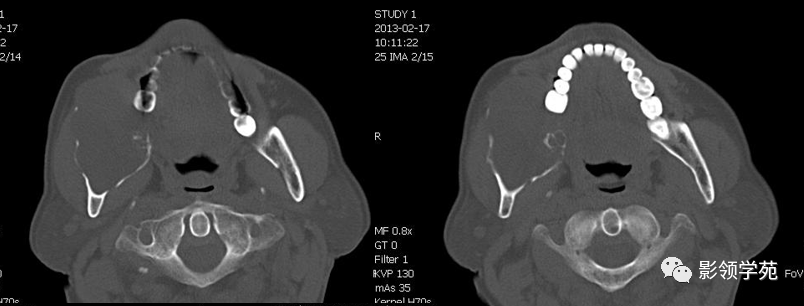

根尖囊肿

大多数是由根尖慢性感染所致,是齿源性囊肿中最常见者。牙周膜上皮细胞受炎症刺激而增殖,其内层上皮细胞分泌物潴留形成囊肿,一般为单发,偶尔多发。

CT表现:呈囊状膨胀性骨破坏,边缘清晰光整,可见齿根突入囊腔内